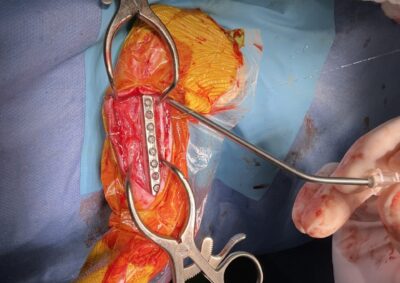

整形外科 注意 ボタンをクリックした先に、治療中および手術中の画像が説明で使用されている場合がございます。 そのような画像に弱い方は閲覧なさらないようお願いいたします。 整形外科 股関節脱臼に対するBUSTOR #65 整形外科 若齢犬の脛骨骨折 整形外科 橈尺骨固定術 #259 整形外科 膝蓋骨内方脱臼 G4 整形外科 膝蓋骨内方脱臼 G2~3 整形外科 橈骨固定術 #258 整形外科 膝蓋骨内方脱臼G3 整形外科 MPL G2 整形外科 CBLO #241 整形外科 膝蓋骨内方脱臼G3 整形外科 LCPDに対するFHNE 整形外科 CBLO#240 × Piezosurgery <12345678> 症例カテゴリー 放射線治療整形外科軟部組織外科脳神経外科内科腫瘍外科救急・集中治療リハビリテーション科腫瘍内科内視鏡科脳神経科呼吸器外科中医・漢方猫の腎移植循環器科